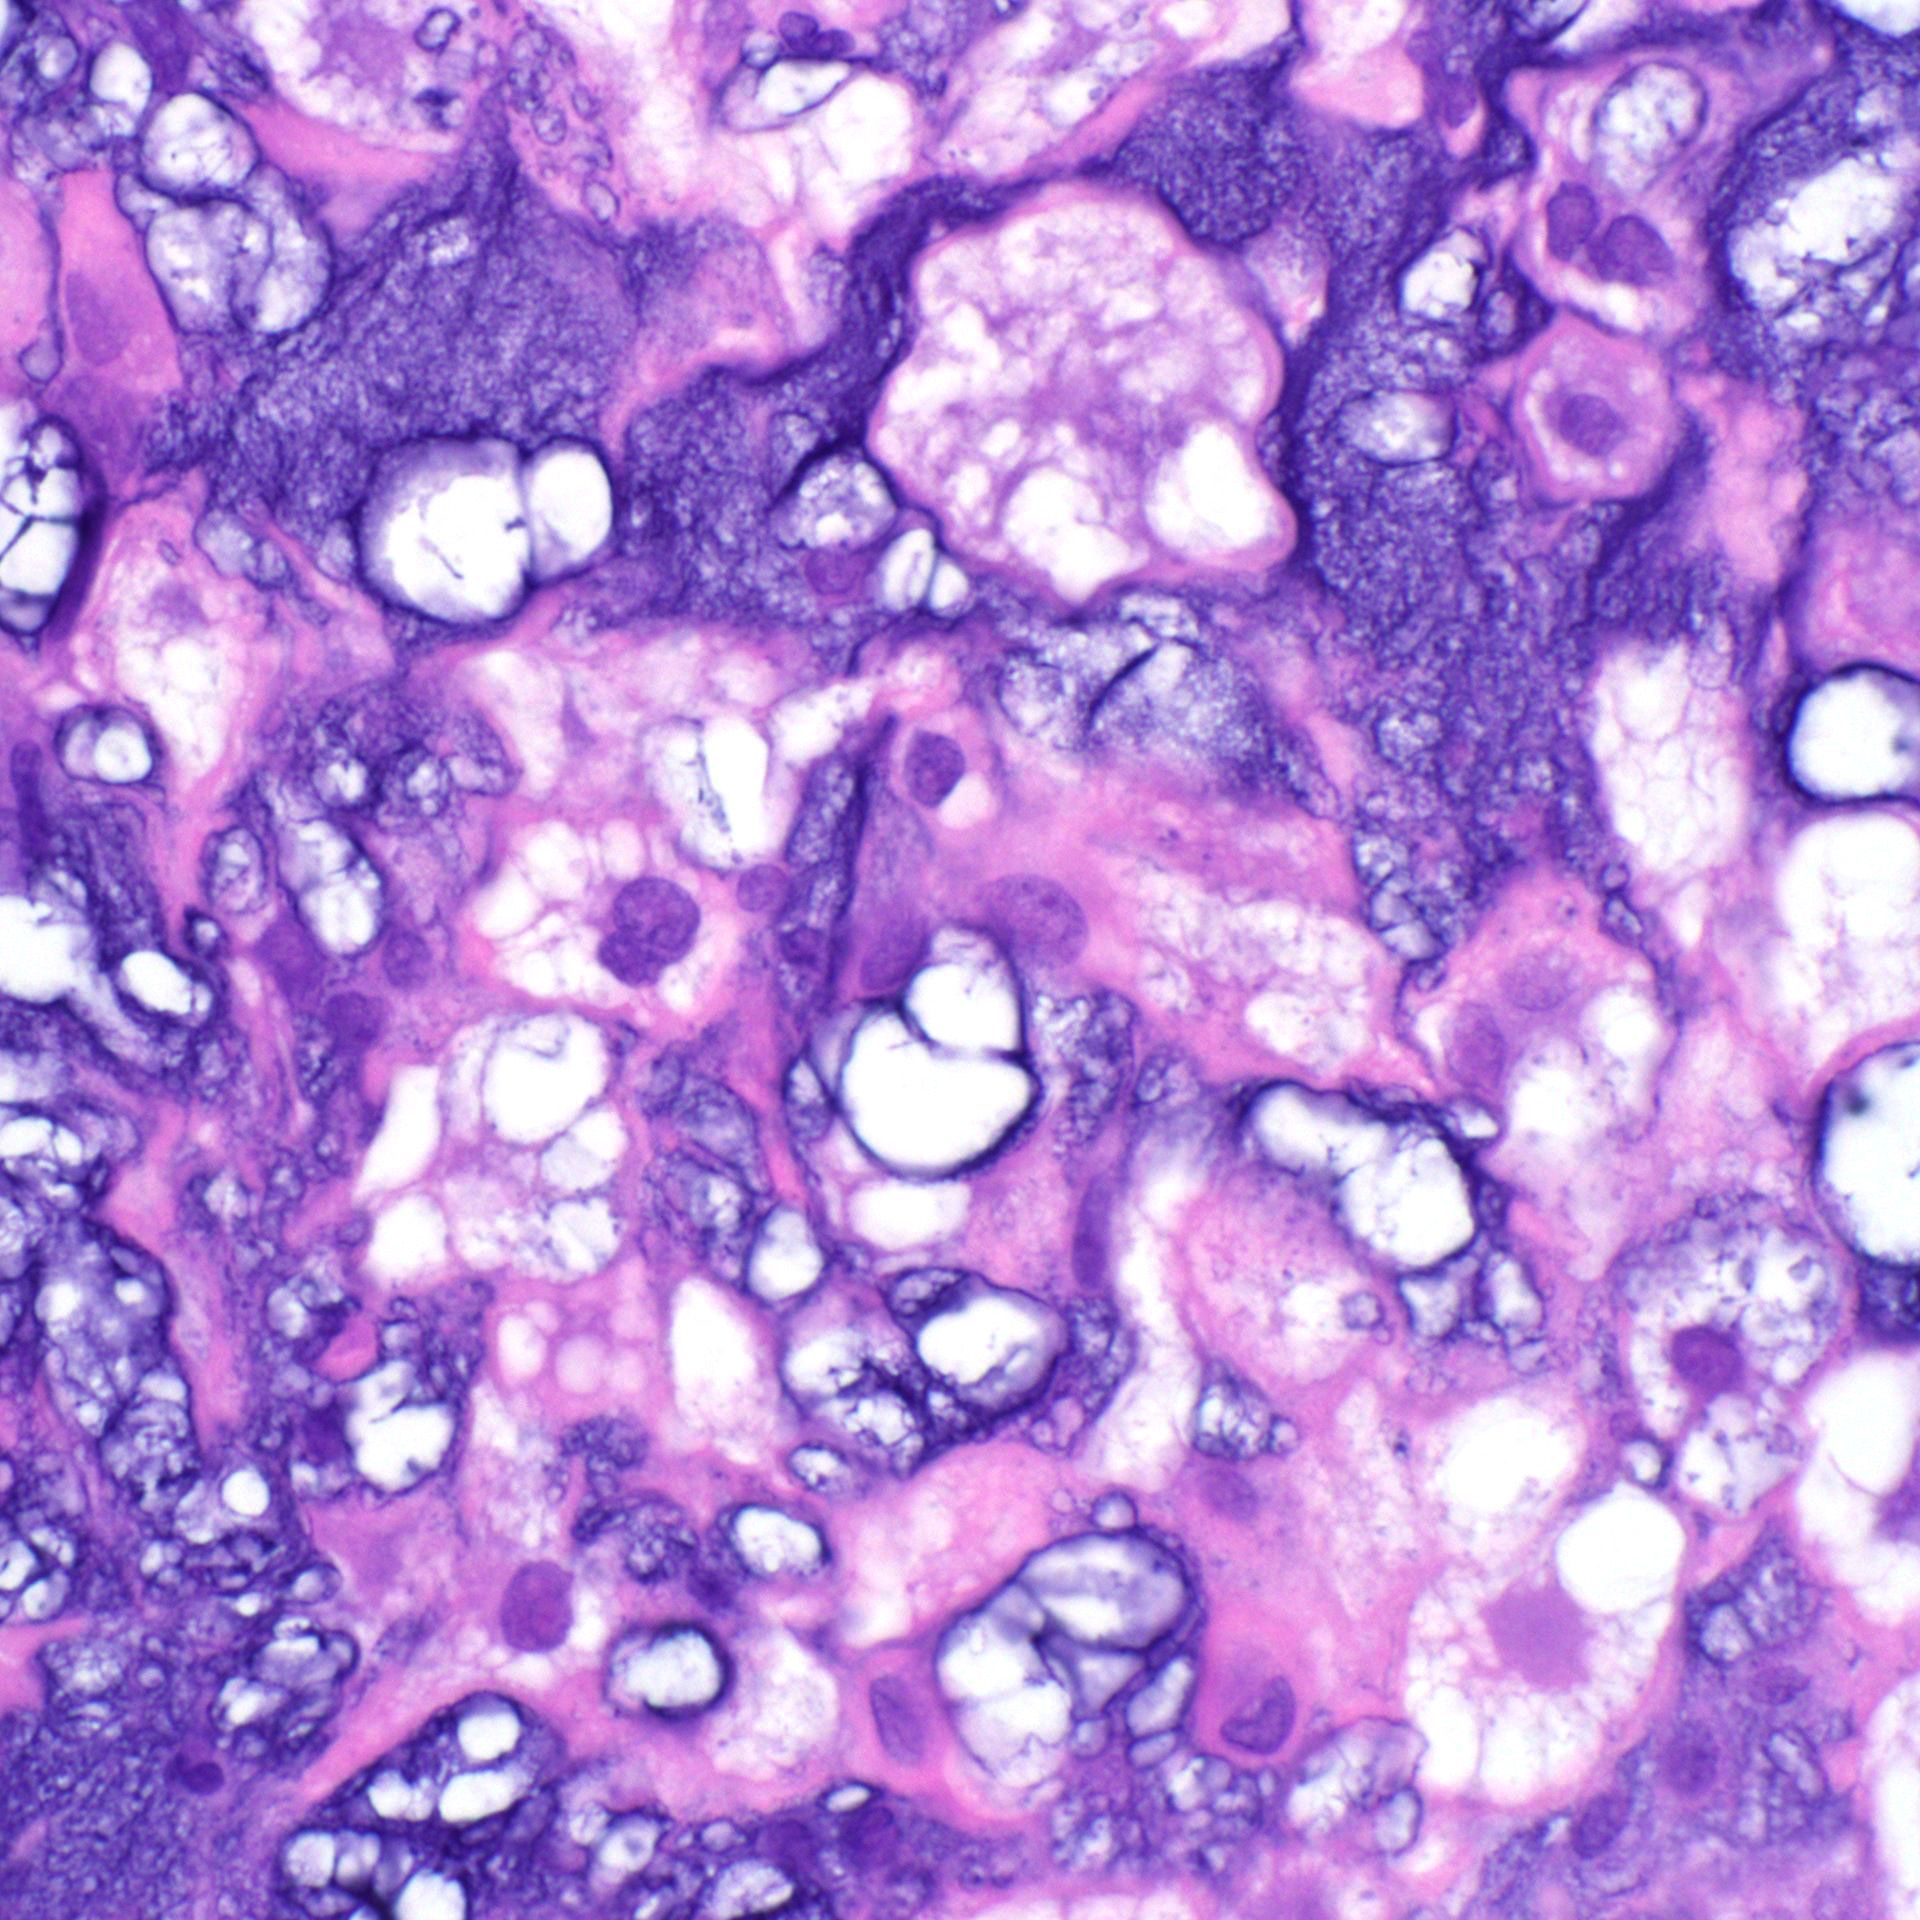

What process is happening here? How old is this patient?

Answers & pics w labels: kikoxp.com/posts/20899